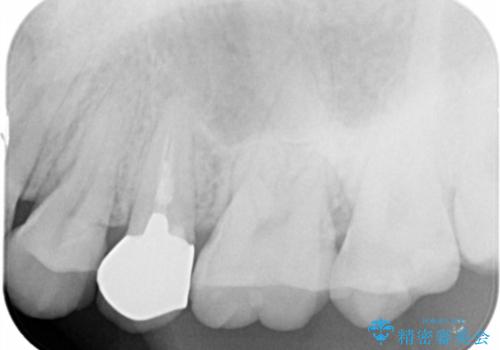

- 歯ぐきの腫れや、歯の内部が黒く見えることからの虫歯の治療を求めて来院されました。

虫歯が大きかったことから、神経の温存はできたものの歯ぐきよりも深い虫歯の問題を解決するため部分矯正治療を併用したセラミック治療を行うこととしました。

当初、歯ぐきよりも深い虫歯のぞんざいや、歯のポジションに問題がありましたがマルチブラケットを用いた部分矯正を行うことで適切な位置へと歯を移動させ、歯周環境を整えたセラミック治療を行うことができました。